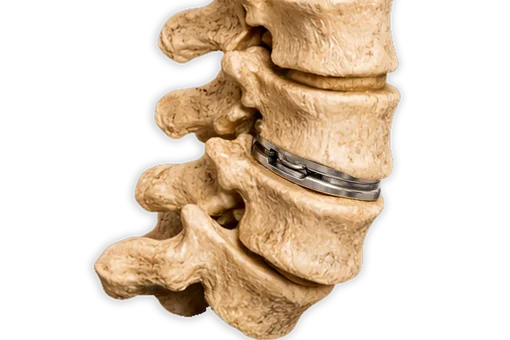

During the further course of the process, substance of the intervertebral disc is decreasing, disc height is diminished, leading, regardless of protrusions and/or herniations, to narrowing of the nerve exits, a lateral narrowing of the spinal canal called lateral stenosis. Advanced stages of degeneration lead to a complete loss of disc height causing complete narrowing of the spinal canal (central stenosis). X-rays and MRI show typical signs as well. Although increased stiffening can be assumed in the advanced stages, segmental instabilities can regularly be found, causing pain.

The spinal canal can be narrowed both laterally and centrally, resulting in spinal stenosis, which can lead to corresponding symptoms and must be treated according to its original cause.